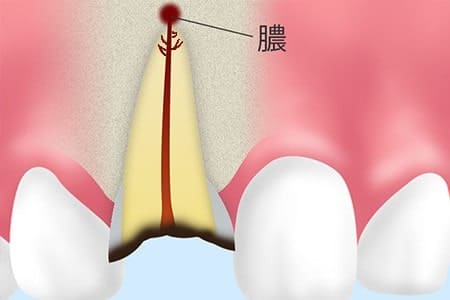

GTR膜を使った再生療法

GTR膜という特殊な膜を使って骨の再生を助ける治療法です。骨は成長が遅いため、骨ができて欲しいところに成長の早い肉や歯ぐきが入り込んできてしまいます。そこで、GTR膜というバリアを置くことで、望ましくない組織の侵入を防ぎ、骨がゆっくりと中で成長できるように環境を整えていく再生療法がGTR法です。

インプラント治療の場合も同様に、膜を使って骨の高さや幅が足りない場所に骨を作る治療をした後にインプラント治療を行うことで、長期的に安定性の高い環境を作ることができます。